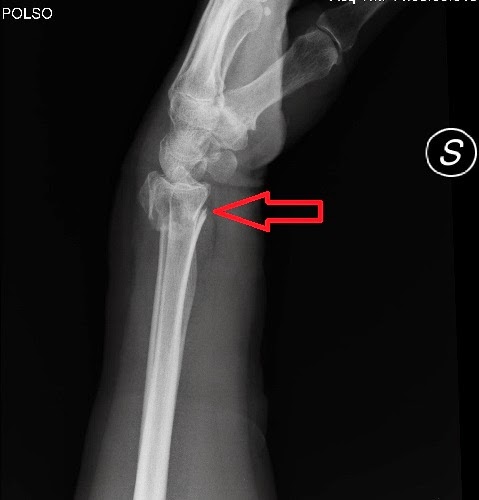

Frattura Di Goyrand. Frattura di goyrand polso sx. Contenzione in gesso brachio-metacarpale BM della frattura di polso sx. Dorso della mano invece che sul palmo della mano e il frammento radiale distale si disloca ventralmente invece che dorsalmente. È invece identica la sede e il decorso della rima di frattura.

La frattura di polso e una delle piu frequenti patologie da trauma che richiede una immobilizzazione immediata una riduzione incruenta oppure un vero intervento chirurgico con placcafili di kirschner o fissatore esterno. Seguivano ulteriori controlli clinici specialistici di cui appare disponibile la seguente documentazione. Manovra progressiva senza strappi attenzione alla cute dei pz. Una delle più comuni fratture è la frattura detta di Colles in cui il frammento rotto si porta verso lalto. La Frattura di Goyrand-Smith GSF detta anche solamente Smith Fracture fa parte delle Fratture distali del RadioPer la prima volta è stata descritta da Robert Williams Smith nel 1847 1. La frattura di Goyrand o di Colles inversa come suggerisce il nome presenta i segni clinici inversi a quella di Colles classica.

Una frattura da fabbro è nota con pochi altri nomi come una frattura di Goyrand e una frattura di Colles inversa. Sede e decorso della rima di frattura sono identiche ma in questo caso il frammento osseo distale si palmarizza spostamento verso il palmo della mano. Chiama subito per fissare un appuntamento in uno dei nostri centri di Fisioterapia Italia la valutazione è GRATUITA. La frattura di Goyrand-Smith è una frattura extra- articolare del radio con una dislocazione o angolazione volare della rima di frattura distale. Tipica frattura delle cadute sul palmo della mano in estensione. Manovra progressiva senza strappi attenzione alla cute dei pz.

Contenzione in gesso brachio-metacarpale BM della frattura di polso sx. Tipico delle cadute con il palmo della mano flesso. Solitamente viene trattato mediante. Dorso della mano invece che sul palmo della mano e il frammento radiale distale si disloca ventralmente invece che dorsalmente. È invece identica la sede e il decorso della rima di frattura.

I sintomi di un polso rotto possono includere. Ma le fratture di Smith sono in realtà piuttosto rare. I casi in cui la frattura di Radio coinvolga solo la Stiloide Radiale fig. Si verifica per la. La frattura di Goyrand-Smith è una frattura del radio distale anche detta frattura di Colles inversa in quanto la dislocazione del frammento epifisario nel piano sagittale avviene in senso inverso.

La frattura di Goyrand-Smith è una frattura del radio distale anche detta frattura di Colles inversa in quanto la dislocazione del frammento epifisario nel piano sagittale avviene in senso inverso. Frattura di goyrand polso sx. Si presenta dopo una caduta accidentale con la mano atteggiata in flessione. è chiamata anche frattura di Colles Inversa in quanto la dislocazione del frammento di frattura della metafisi distale del radio avviene in senso opposto. La frattura di polso per lungo tempo è.

La frattura con le deformità opposte si definisce di Goyrand. Frattura di Goyrand-Smith. Si verifica per la. è chiamata anche frattura di Colles Inversa in quanto la dislocazione del frammento di frattura della metafisi distale del radio avviene in senso opposto. FRATTURA DI GOYRAND Più rara della frattura di Colles è detta anche Colles inversa.